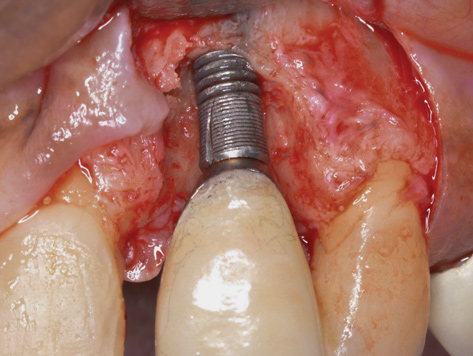

(7.) Because apical and lateral bone volume was preserved with use of an ultrathin trephine, a wider diameter, 4.2-mm implant was placed at the time of implant removal. Bone augmentation was performed, and submerged healing was selected.

Figure 7

Occasionally, when a fractured implant is removed via a trephine drill, a wider implant can be placed that will still be within the osseous envelope and respectful of physiologic and esthetic guidelines (Figure 6 through Figure 10). After explantation of an implant with a 3.6-mm diameter body that tapered to 2.5 mm apically, a coronally tapered 4.2-mm diameter implant with a 2.5-mm apical diameter (Astra Tech, Dentsply Sirona) was placed with adequate implant stability. The facial bone lost secondary to the fracture was augmented simultaneously with immediate implant replacement.